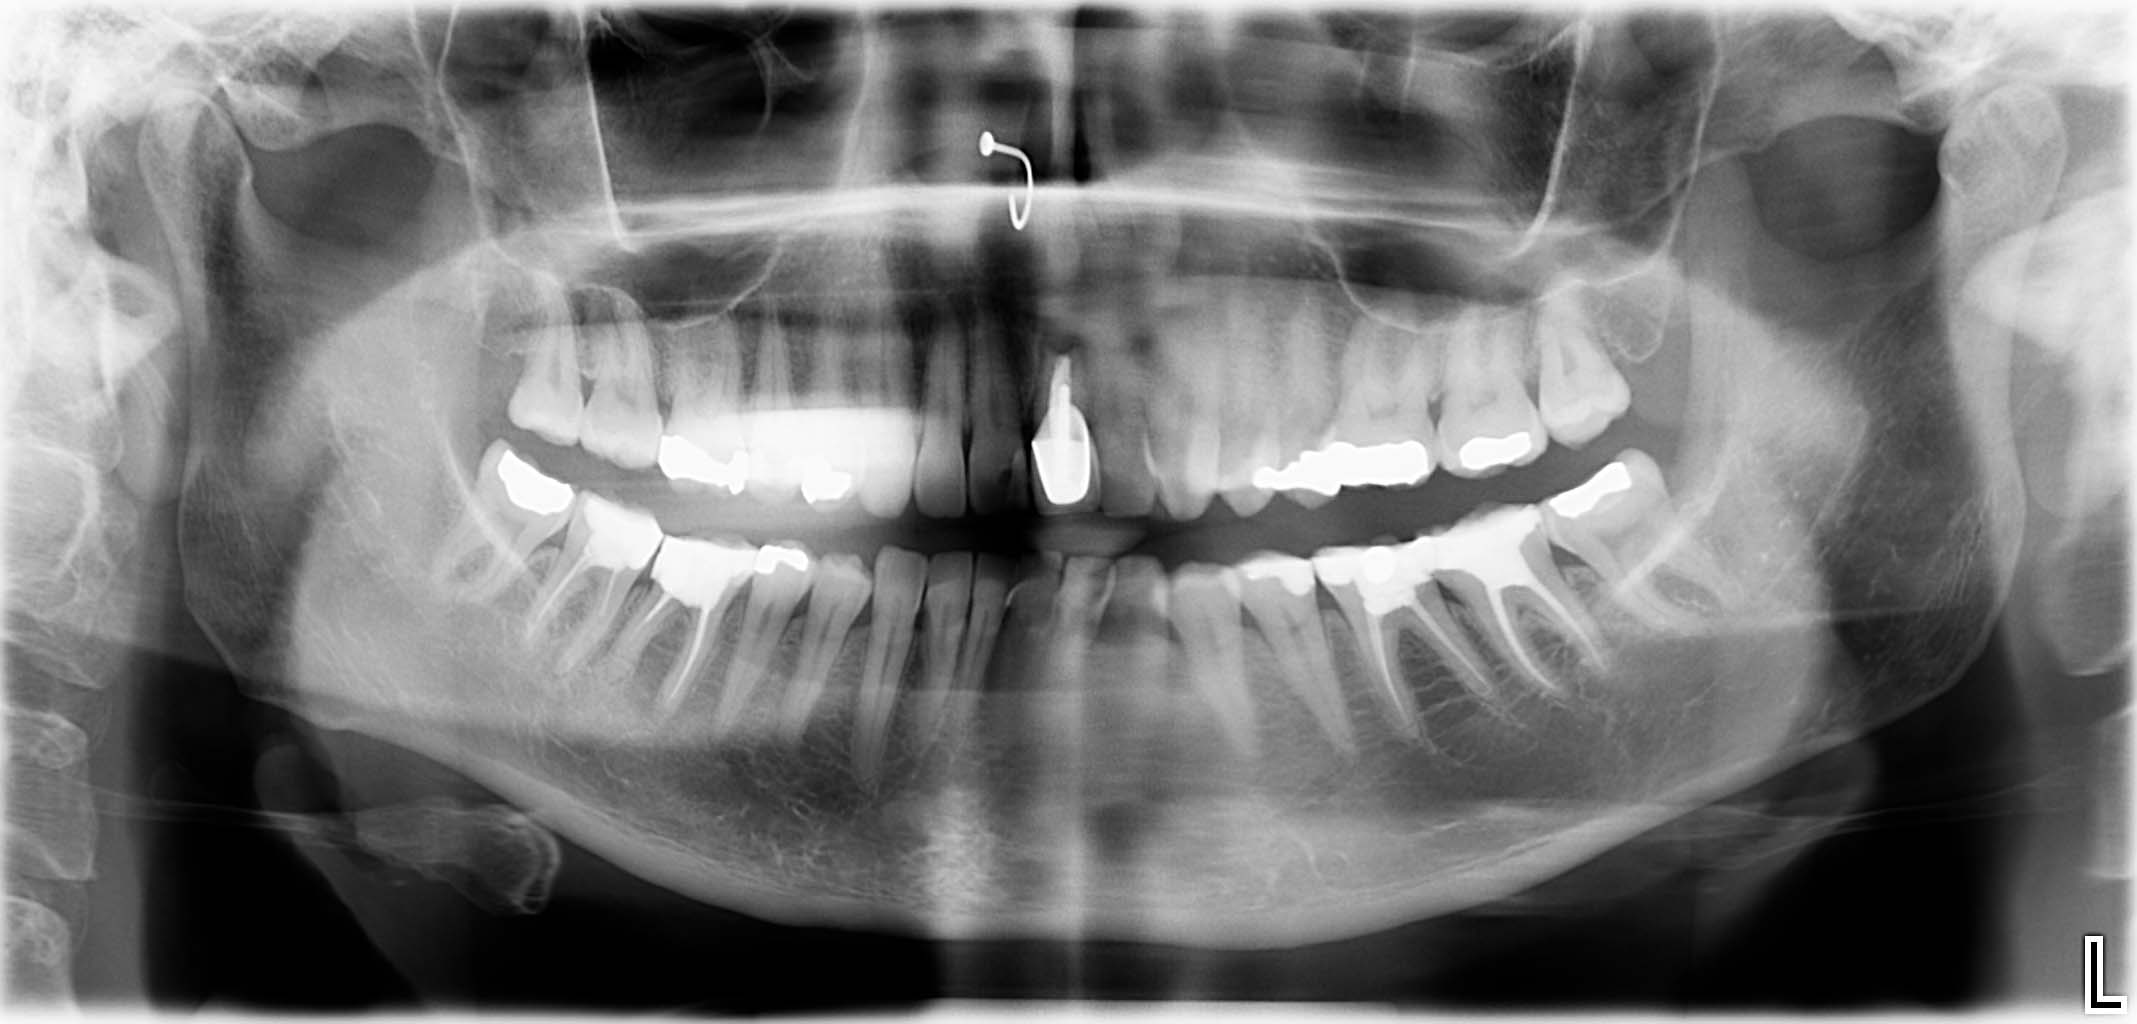

Erfolgreich implantierte Patientenfälle (klinische Fotos)